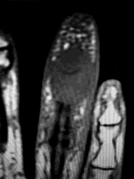

Question 10:

A 15-year-old boy presents with knee pain. Imaging reveals a destructive metaphyseal lesion of the distal femur with a sunburst periosteal reaction. Staging shows no metastasis. Following neoadjuvant chemotherapy and wide surgical resection, what is the most significant prognostic factor for overall survival?

Correct Answer: Percentage of tumor necrosis on histologic map

Explanation:

In osteosarcoma, the histologic response to neoadjuvant chemotherapy, measured as the percentage of tumor necrosis in the resected specimen, is the most powerful predictor of disease-free and overall survival. A good response is typically defined as greater than 90% tumor necrosis.